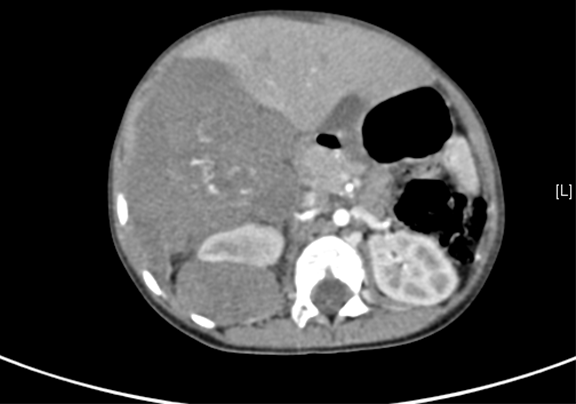

上腹部增强CT示:肝右后叶-右肾上腺区-右肾上极区域占位,考虑恶性肿瘤,肝母细胞瘤?并腹膜后转移。

将0.625mm双源薄层CT资料的静脉期和动脉期Dicom格式文件导入海信CAS系统。

通过调节窗宽窗位调整CT序号,对肿瘤,肝实质,胆囊,下腔静脉,肿瘤,肝动脉、门静脉及肝静脉等进行三维重建;系统自动计算肿瘤体积和肝脏体积。

模拟手术操作,自动计算切除肿瘤体积。肝脏体积为660.9ml,肿瘤体积为812.3ml,肿瘤体积为肝脏体积的122.9%,通过比对3-4岁正常肝脏体积为522.63±121.24 ml,肿瘤所占比例较大,且包裹右侧肾脏、及腹腔大血管,手术无法完整切除肿物,不建议给予手术治疗。

术前CT检查:

动脉期

静脉期

平衡期